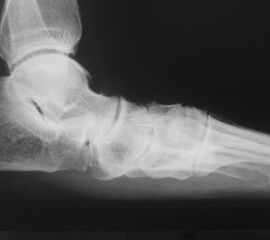

Die Operation erfolgt meist über einen medialen Zugang. Nach Entknorpeln der  Gelenkflächen und Anfrischen des subchondralen Knochens kann die Arthrodese mit Schrauben oder Plattensystem erfolgen (Abb. 5). Bei Fehlstellungen muss diese vor der Osteosynthese korrigiert und das Talonavikulargelenk reponiert werden. Pseuarthrosen werden hier zwischen 8-25% angegeben 3223.